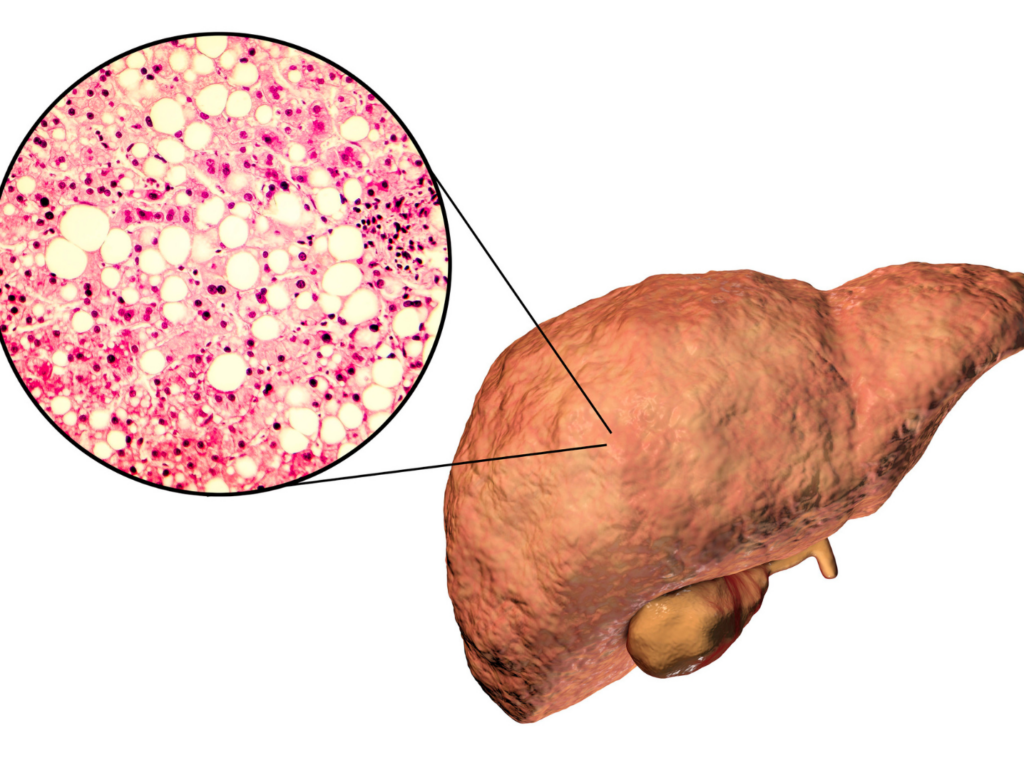

- Sử dụng rượu và thuốc lá thường xuyên: Sử dụng rượu lượng lớn và thường xuyên có thể gây tổn thương gan và dẫn đến viêm gan mạn tính và xơ gan. Gan cũng có thể bị tổn thương bởi các chất độc gây ung thư có trong thuốc lá. Hút thuốc lá góp phần vào sự phát triển của các bệnh gan mạn tính, bao gồm xơ gan.

- Béo phì: Người béo phì có nhiều khả năng bị gan nhiễm mỡ và đái tháo đường, cả hai đều có liên quan đến ung thư gan.